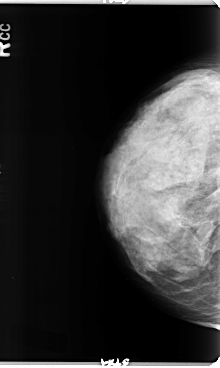

B_3358_1.RIGHT_CC

RIGHT_CC LINES 4784 PIXELS_PER_LINE 2848 BITS_PER_PIXEL 12 RESOLUTION 50 NON_OVERLAY